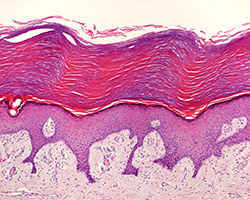

Piel

Piel

Piel fina y gruesa, glándulas anejas, pelo, uña y mama.

(14 preparaciones) -